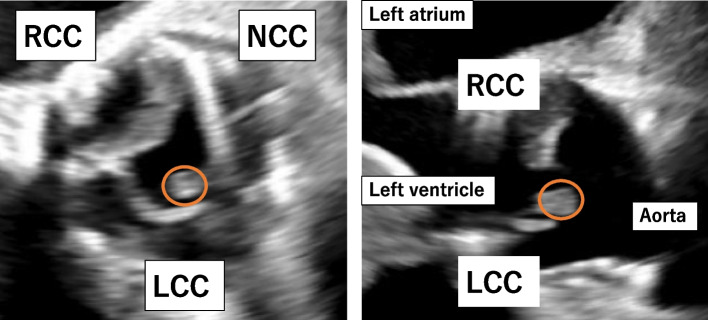

Case presentation: We report the case of a 73-year-old woman who had previously undergone sutureless valve implantation for severe stenosis of a bicuspid aortic valve. Approximately 23 months after surgery, the patient developed recurrent Methicillin-resistant Staphylococcus aureus bacteremia and was admitted to the hospital. Following a thorough assessment, she was diagnosed with a prosthetic valve infection and an annular abscess, necessitating surgical intervention. Intraoperatively, significant annular destruction was evident after the valve was removed. The aortic root was reconstructed with a bovine patch and Bentall surgery was accomplished using a composite graft consisting of a biological valve and a Valsalva graft. The patient was discharged in good general condition with no significant post-operative complications.